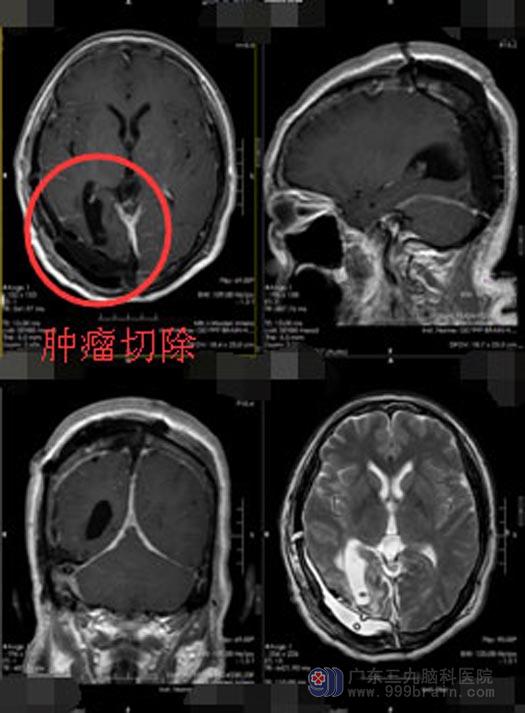

手术很顺利,由于复发的肿瘤切除得干净,手术后的李阿姨精神状态也越来越好,不久就可以康复出院。